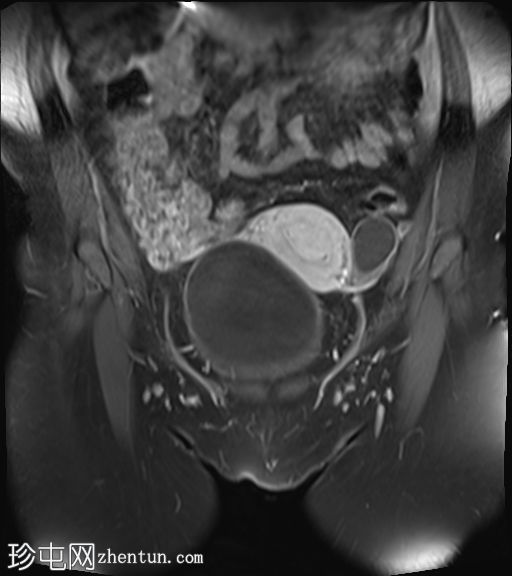

冠状位

T2加权像

4.jpg

子宫体积增大,宫底可见息肉样病变,T2加权像呈异常中高信号强度。病变可见轻度扩散受限,增强后呈均匀强化。病变与宫底交界区之间可见一界限清晰的异常高T2信号区域,可能为囊性变性。未见病变超出交界区。

在剖宫产切口远端的前壁上,可见另一处类似的较小病灶。

左侧附件囊性病变,T1加权像信号异常低,T2加权像信号异常高。无增强扫描强化。

子宫内膜息肉是子宫内膜组织的结节状突起。通常表现为T2加权像信号异常高,增强扫描后呈均匀强化。

病理检查通常显示增生期子宫内膜紊乱。